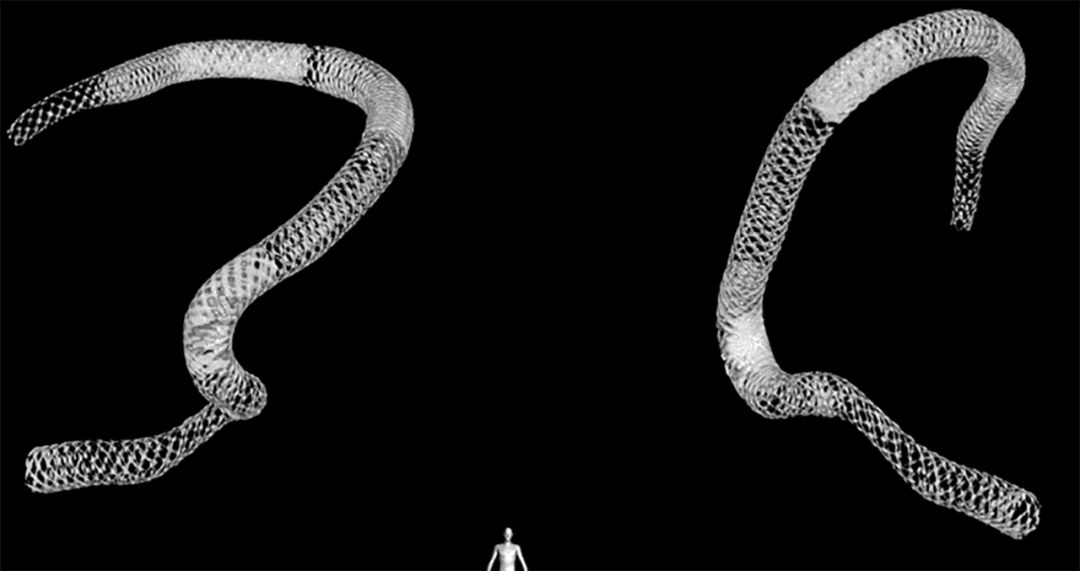

该患者脑部巨大长夹层动脉瘤,直径约17 mm,长度约65 mm,治疗极为棘手极富挑战,常规治疗失败率高复发率高,是复杂脑动脉瘤治愈利器--密网支架临床攻关克难的优选病例。

本例介入手术共使用4枚长密网支架桥接放置治疗巨大长夹层动脉瘤,手术顺利,术中清晰可见支架桥接与放置打开情况,微创介入手术大约一个多小时,术后三天患者无任何后遗症步行出院,患者术后半年CTA血管造影复查,脑动脉瘤顽疾得以治愈,脑血管形态已经基本恢复正常 ,患者恢复良好,生活完全正常并重返工作岗位。

(1)右侧颈内动脉海绵窦段至颈内动脉末端巨大夹层动脉瘤伴血栓形成(图1)。

图1

(7)支架重建后正侧位(图10)。

图10